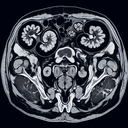

Магнітно-резонансна томографія (МРТ) нирок — це неінвазивний метод обстеження, який використовує магнітне поле та радіохвилі для отримання детальних зображень нирок і навколишніх структур. Ось кілька ключових аспектів: 1. **Безпечність**: МРТ не використовує іонізуюче випромінювання (радіацію), що робить його безпечним для пацієнтів...